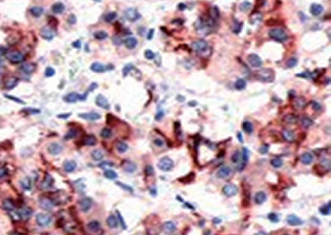

| 预处理:高pH热修复 | 阳性部位:细胞浆 | 阳性对照:胎盘/垂体瘤 |

| 垂体瘤石蜡切片,用 PRL(GT2161)染色,细胞浆阳性,DAB 显色。 | ||